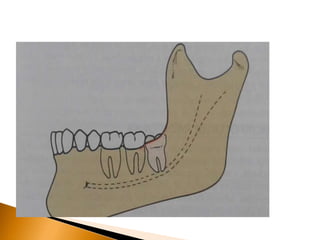

Perda óssea resultante da

presença do terceiro

molar

 Pacientes com terceiros

molares

 inferiores impactados

freqüentemente têm bolsas

periodontais profundas na

região distal do segundo

molar, ainda que tenham

profundidade sulcular

normal no restante da boca.

 O problema periodontal

acelerado que resulta da

impactação do terceiro

molar é especialmente sério

na maxila.

Grave perda óssea resultante

de doença periodontal e do terceiro